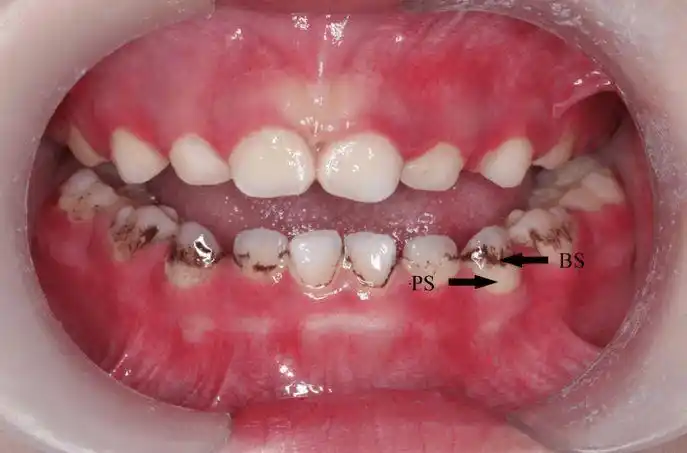

宝宝牙齿黑了,怎么办?_儿童牙病_儿童牙病相关疾病 - 好大夫在线

宝宝牙齿上有很多黑色斑块,是虫牙吗?

宝宝牙齿色素沉着怎么处理